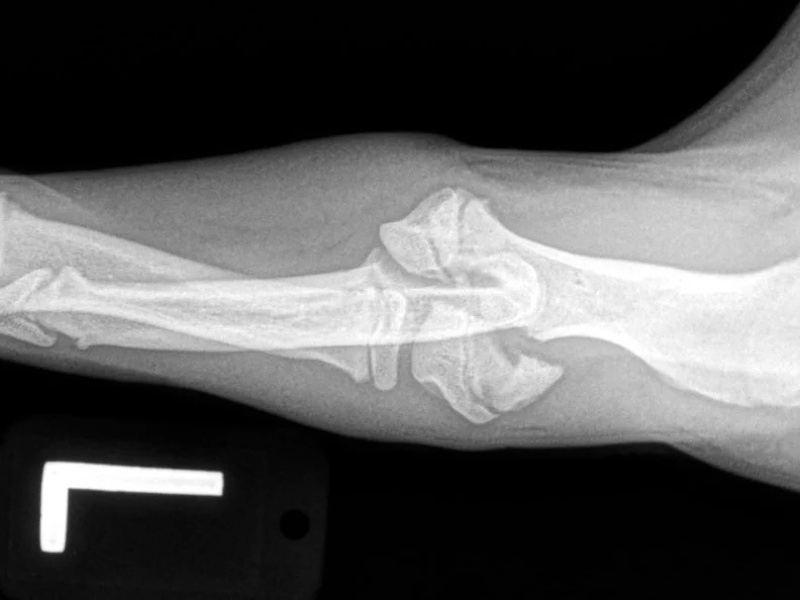

Carpal Hyperextension